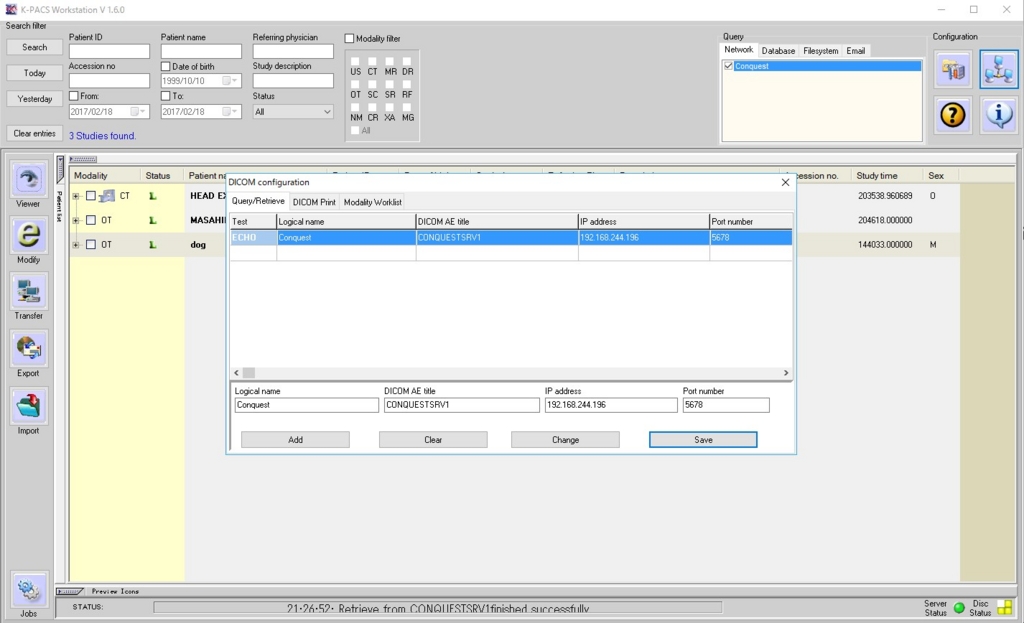

クライアント側の設定も忘れずに。

これでKPACSとConquestが接続されているはずです。

今度はホストPC上のクライアントソフト(KPACS:DICOMviewer)の設定です。

右上のDICOMsettingボタンを押して、DICOMconfigurationsで、仮想マシンのIPアドレスを入力し設定保存します。

KPACSのQuery→Networkタブを選択→Conquestにチェック→Search filterのSearchボタンを押してみましょう。テストデータが見えました。

接続成功です。